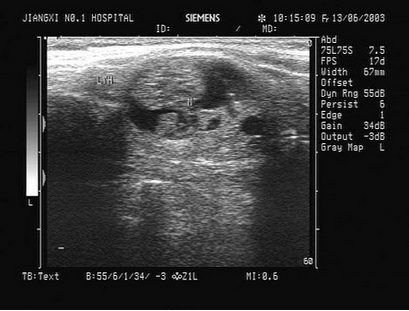

某患者脾脏声像图表现如图,诊断为()

A.正常脾脏

B.脾大

C.脾破裂

D.脾梗死

E.以上都不是